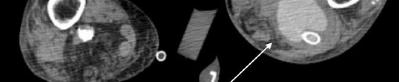

Her laboratory studies were notable for a hemoglobin of 11.9 grams per deciliter (g/dL) (reference range: 11.6-15 g/dL) and a normal white blood cell count of 8.4 thousand per cubic milliliter (k/μL) (reference range: 5-10 k/μL). Her lipase and liver function tests were within normal limits. Her human chorionic gonadotropin (hCG) had tripled from 6,253 milli-international units per milliliter (mIU/mL) (reference range: ≤2 mIU/mL) from her prior presentation to 18,038 mIU/mL. Transvaginal ultrasound showed a possible ectopic pregnancy adjacent to the right ovary and no intrauterine pregnancy (Image 1).

The patient declined medical abortion and was taken to the operating room for a right salpingectomy. On her initial presentation 11 days prior, the patient’s preoperative ultrasound had shown a complex focus of the left ovary with a hyperechoic thick rim suggestive of ectopic pregnancy and probable right-sided corpus luteal and anechoic cysts (Image 2, Image 3). No evidence of right ectopic pregnancy was documented intraoperatively during the patient’s initial salpingectomy. Pathology findings from the initial left- and subsequent right-sided procedures showed immature chorionic villi, congestion, and hemorrhage consistent with a tubal

Image 1. This image shows the patient’s ultrasound findings 11 days after her initial diagnosis of a left tubal pregnancy. The image on the left shows the right adnexa with an arrow pointing to a rounded cystic structure with a peripheral soft tissue component, blood flow, and free fluid. The image on the right shows the left ovary with two arrows pointing to a moderate amount of free fluid in the left adnexa. Image 2. This image shows the patient’s initial ultrasound findings. The image on the right shows two arrows pointing to the left adnexa with a complex focus measuring 2.5 x 2.6 x 2.6 centimeters (cm) with a cystic focus of 0.5 cm within it and a hyperechoic thick rim. The image on the left shows the right adnexa with arrows pointing to a small, probable 0.8 cm corpus luteal cyst and an anechoic cyst measuring 1.6 cm.

Image 3. This image shows both of the patient’s ultrasound findings as described above for ease of comparison. The upper panel is from the initial encounter and the lower panel is from the patient’s encounter 11 days later.